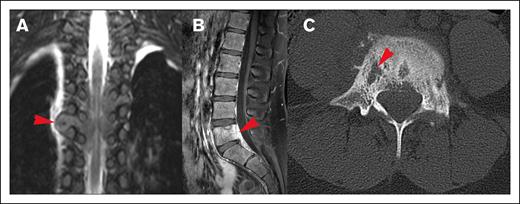

Most lesions (92.7%) extended through the neural foramina of either the vertebrae or sacral bone; 2 lesions did not extend through the neural foramina, and 2 lesions could not be evaluated (Figure 4). Thirty-one lesions entered the spinal canal. Of these, 54.8% caused displacement of the spinal cord, 25.8% were adjacent to the spinal cord but did not cause displacement, and 19.4% did not contact the spinal cord (Figure 5). None of the lesions infiltrated into the spinal cord itself. Spinal cord edema was evaluated for patients who had MRI available (17 of 31 lesions). Among these evaluable lesions, only 12.9% had evidence of spinal cord edema.

Spreading pattern of CNS HL. (A) Tumor spreading through the neural foramina into the thoracic spine. (B) Direct spread from lumbar spinal vertebrae, (C) Lytic cortical bony lesions (same patient as shown in panel B).